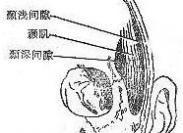

顳間隙感染

628健康網(wǎng)為您分享有關(guān)顳間隙感染的癥狀,顳間隙感染的治療方法,顳間隙感染的預(yù)防知識(shí),顳間隙感染的癥狀圖片,顳間隙感染...

顳下間隙感染

628健康網(wǎng)為您分享有關(guān)顳下間隙感染的癥狀,顳下間隙感染的治療方法,顳下間隙感染的預(yù)防知識(shí),顳下間隙感染的癥狀圖片,顳...